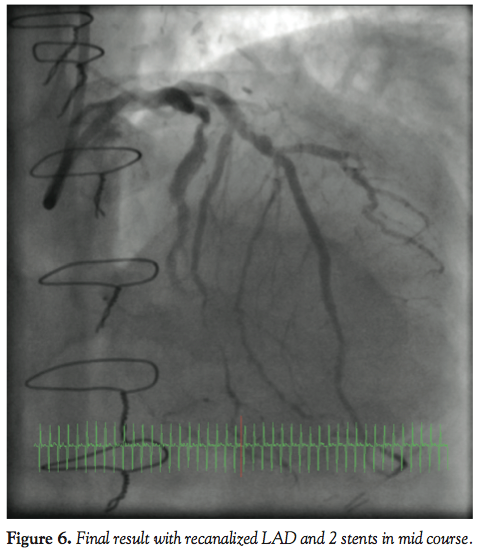

wire (Asahi Intecc) was externalized and the Corsair catheter removed with initial 1.5 balloon dilatation performed retrogradely (Figure 5). Further 2.0 balloon dilatation was performed antegradely and subsequently 2 Promus Element DESs (Boston Scientific) were deployed and the distal LAD was treated with plain old balloon angioplasty with the 2.0 balloon, with excellent final results (Figure 6). The patient tolerated the procedure well with no complications and was monitored on the ward and allowed home in a stable condition.